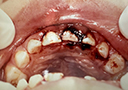

2歳児・前歯の大きなむし歯の治療例

虫歯が大きく歯肉が膿んでしまっています。

膿みを取り除くために神経の処置をします。

その後に歯の形をつくります。